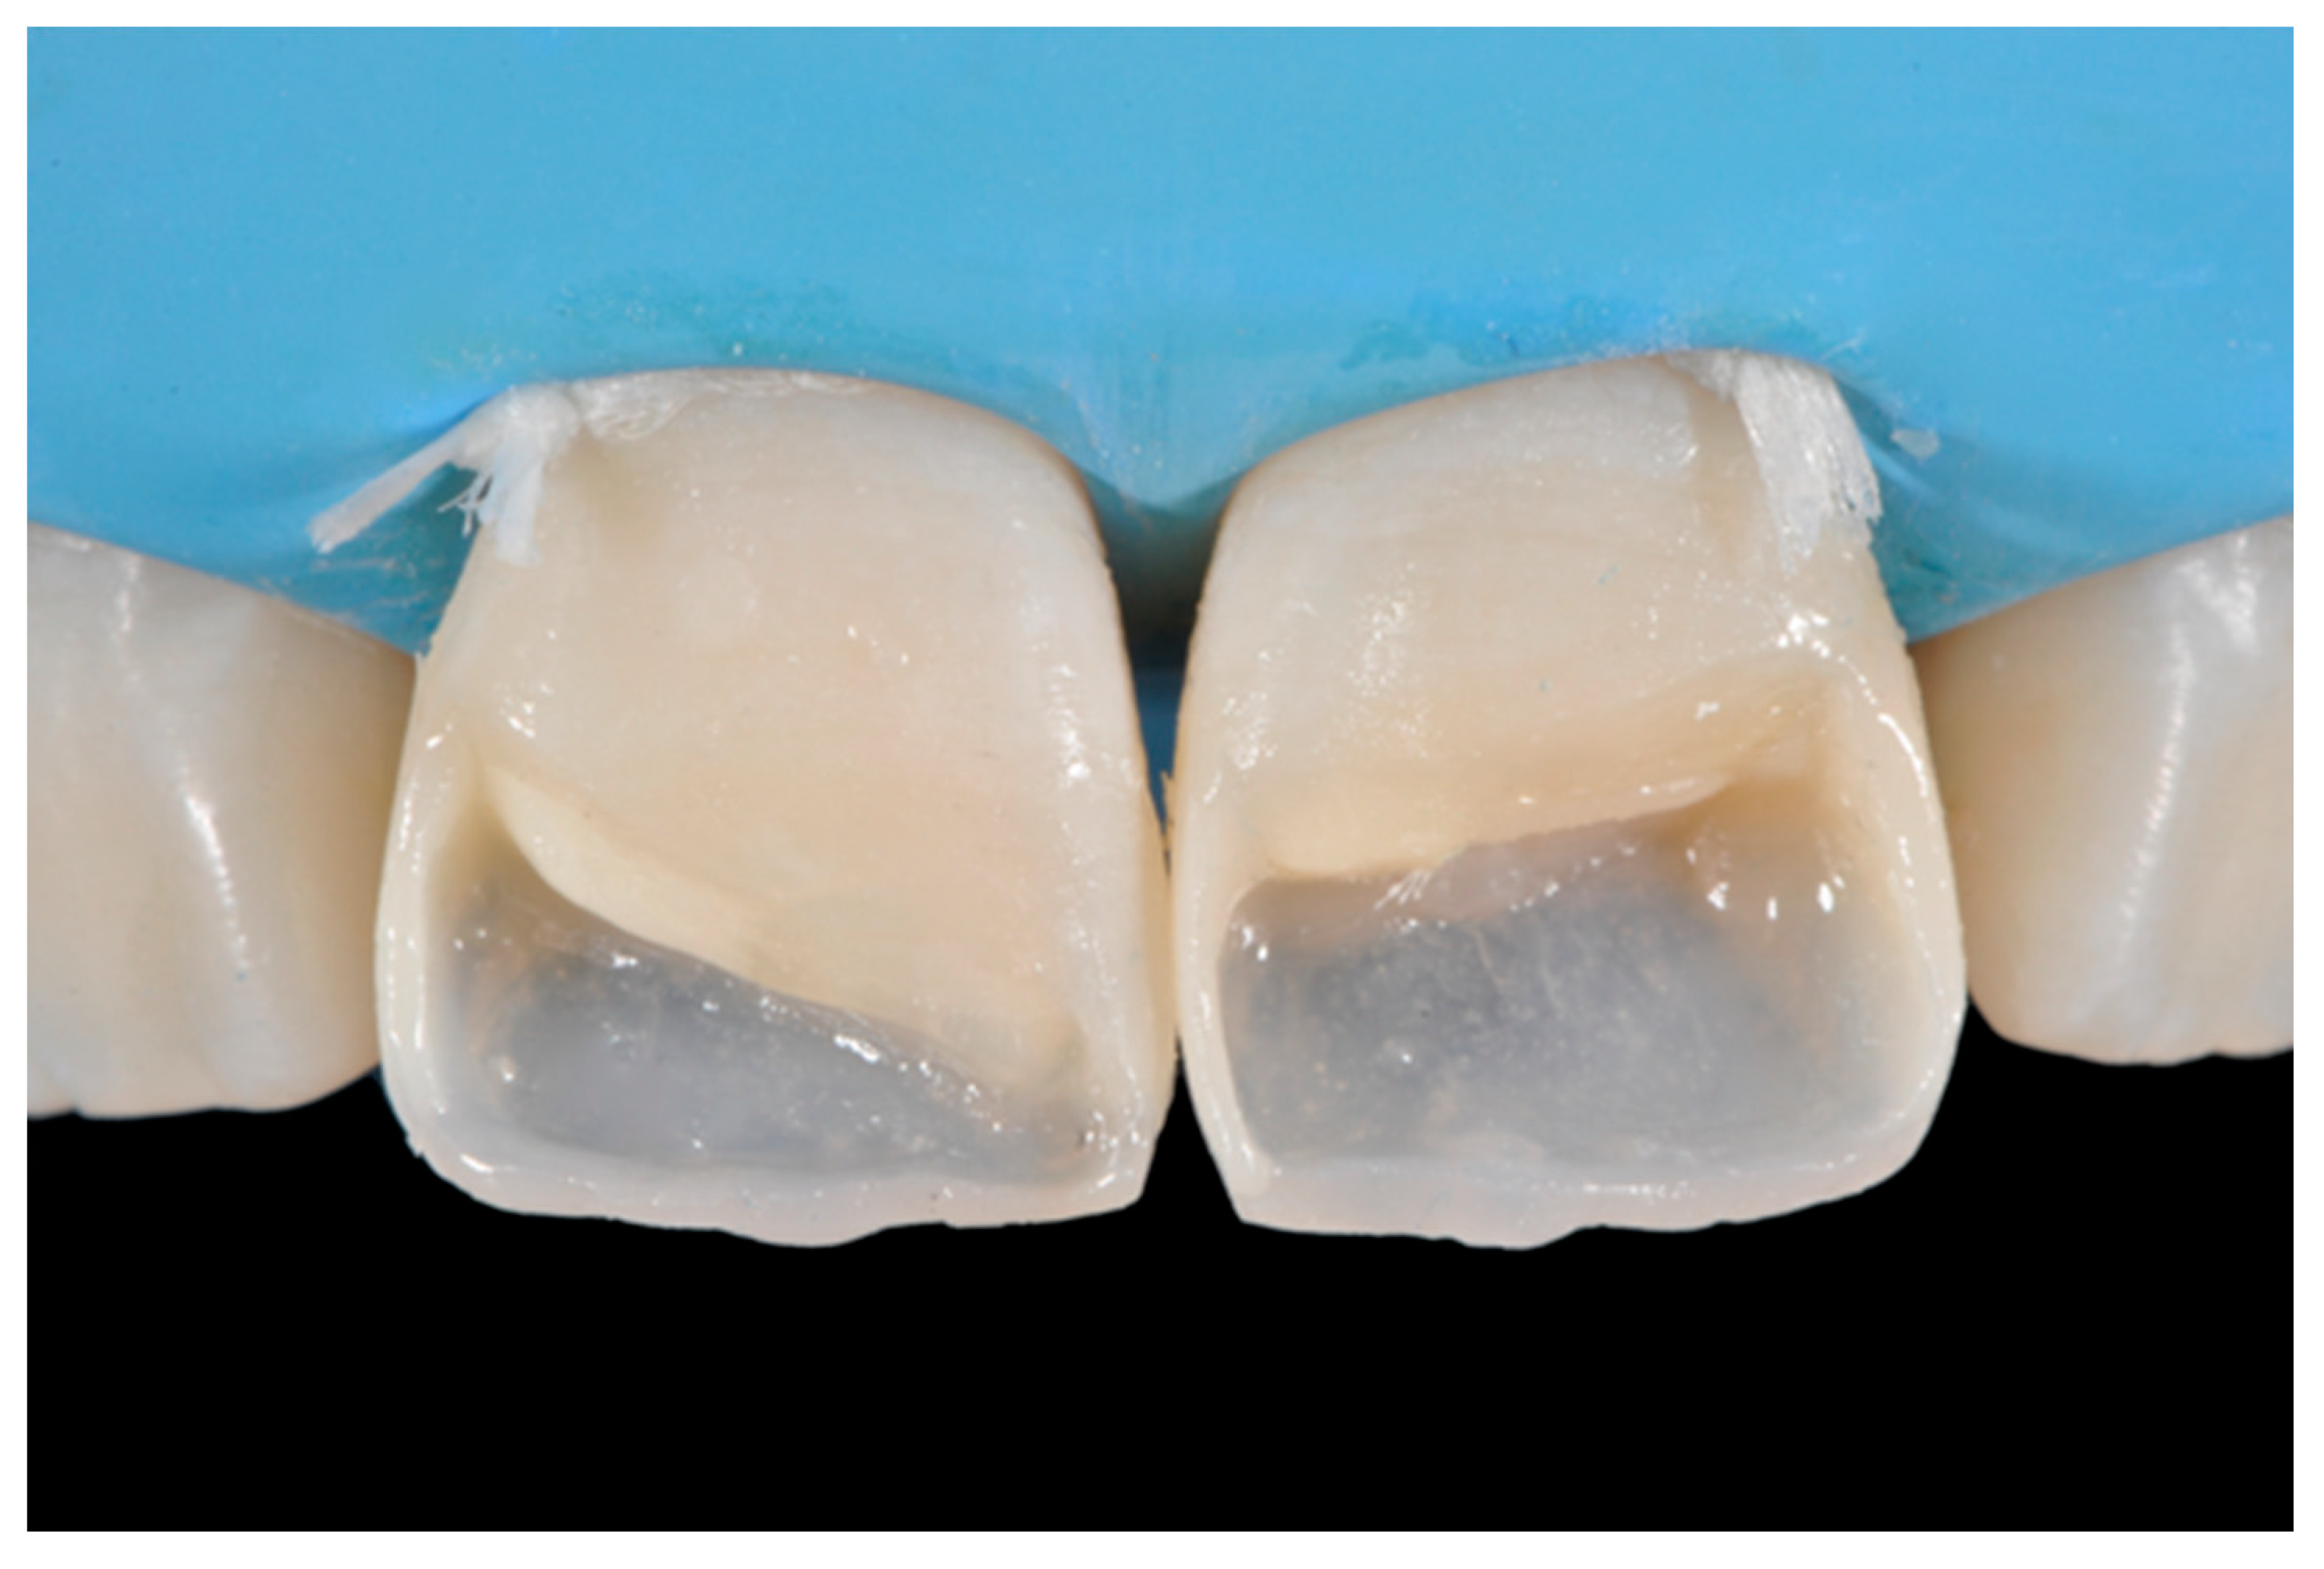

Once completed, the two frames (Clearfil Majesty ES-2, A1E, A2D, Kuraray Noritake Dental, Tokyo, Japan) showed internal and external excesses that were reduced using diamond burs and discs (Figure 33 and Figure 34) strictly following the procedure described in Section 2.1.2 of present article. Excesses were removed from the distal-incisal angle of #2.1 allowing therefore to obtain the desired translucency. After silane application and bonding procedure (Figure 35) as described in Section 2.1.2, restorations were completed (Figure 36 and Figure 37). They both show satisfactory clinical integration 1.5 years post-operative (Figure 38 and Figure 39).

Figure 35.

The modified frames treated with silane coupling agent and adhesive, ready for layering of dentinal body. Reprinted from Restauri diretti nei settori anteriori, G. Paolone, S. Scolavino, © 2021, with permission from Quintessence Publishing Italy.